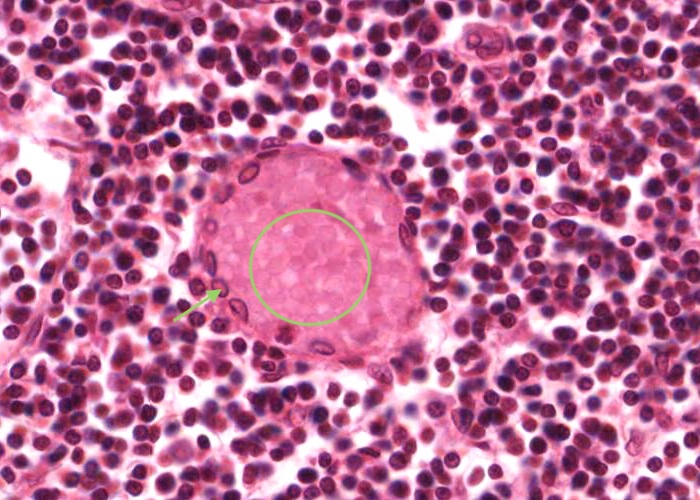

Look at a lymphatic nodule in the cortex. Identify a germinal centre and the corona (mantle) around it.

Look at the nodules in the cortex. Identify a germinal centre and the corona (mantle) around it. Most of the cells in the corona are small lymphocytes. In contrast, many of the cells in a germinal centre of the nodule have large, pale nuclei. This is why a germinal centre stains palely.

The maximal magnification is barely adequate. Scan the cortex for a germinal centre in which the cells are not jammed too heavily on top of one another.

If you see a large, pale nucleus which seems to have no cytoplasm at all around it then it is most likely a follicular dendritic cell. These cells actually have a lot of cytoplasm but it is stretched out into long arms that extend out of the plane of section. Their function is to hold antigen molecules on their surface and "present" them to lymphocytes. They are one type of antigen presenting cell. Various other cell types also present foreign or self antigens.

More rarely you will see nuclei as large as those of dendritic cells, but darker and with a discrete rim of basophilic cytoplasm. The cytoplasm will have a sharp outer perimeter. These cells are lymphoblasts. Their edges are visible because they do not have cytoplasmic arms sticking out.

Small lymphocytes dominate the corona. You can also find occasional prolymphocytes, with more, basophilic cytoplasm than small lymphocytes and with larger, paler nuclei. The supporting reticular cells have elongate nuclei. You also may come across a plasma cell or two.

Finally there are substantial numbers of small lymphocytes each with a circular, dark-stained nucleus.